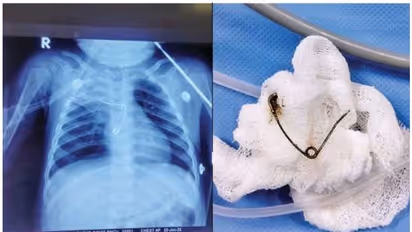

ബോധരഹിതമായ അവസ്ഥയിലാണ് കുഞ്ഞിനെ ആശുപത്രിയില് എത്തിച്ചത്. ഉടന് വെന്റിലേറ്ററിലേക്ക് മാറ്റി. പരിശോധനയ്ക്കിടെ തലച്ചോറില് പഴുപ്പ് കണ്ടെത്തി. ശസ്ത്രക്രിയക്കൊരുങ്ങിയ സമയത്താണ് കുട്ടിക്ക് കൊവിഡ് സ്ഥിരീകരിച്ചപിന്നീട് കൊവിഡ് ഐസിയുവിലേക്ക് മാറ്റി. കൊവിഡ് നെഗറ്റീവായ ശേഷം ന്യൂറോ സര്ജറി വിദഗ്ധര് തലച്ചോറിലെ പഴുപ്പ് നീക്കം ചെയ്തു. ഇതോടെ കുട്ടിയുടെ ആരോഗ്യനില മെച്ചപ്പെട്ടു. പിന്നീട് നടത്തിയ വിശദപരിശോധനയില് അന്നനാളത്തില് സേഫ്റ്റി പിന് കുടുങ്ങിക്കിടക്കുന്നതായി കണ്ടെത്തി. ഉടന് ശിശുരോഗ ശസ്ത്രക്രിയാവിഭാഗത്തിന്റെ നേതൃത്വത്തില് കുഞ്ഞിനെ അടിയന്തരശസ്ത്രക്രി ചെയ്ത് പിന് പുറത്തെടുത്തു. തുറന്ന നിലയിലായിരുന്നു സേഫ്റ്റി പിന് കുടുങ്ങിക്കിടന്നത്. അന്നനാളത്തിലെ പഴുപ്പും നീക്കം ചെയ്തു. സേഫ്റ്റി പിന് അന്നനാളത്തില് കുടുങ്ങിയതിനെത്തുടര്ന്നുണ്ടായ പഴുപ്പാണ് തലച്ചോറിലേക്കും വ്യാപിച്ചതെന്ന് ഡോക്ടര്മാര് പറഞ്ഞു. സേഫ്റ്റിപിന്നും നീക്കം ചെയ്തതോടെ കുട്ടി അപകടനില തരണം ചെയ്തു. ഇപ്പോള് ഭക്ഷണം കഴിക്കുന്നുണ്ട്. അടുത്ത പത്ത് ദിവസത്തിനുള്ളില് ആശുപത്രി വിടാനാകുമെന്നും ഡോക്ടര്മാര് പ്രത്യാശ പ്രകടിപ്പിച്ചു.

ന്യൂറോ സര്ജറി വിഭാഗം മേധാവി ഡോ. ആര്. ബിജുകൃഷ്ണന്, ഡോ. ജിയോ സനില്, ഡോ. ജിതിന്, ഡോ. അമോല് ഡാഗെ, ഡോ. ഷാഹിദ്, ശിശുരോഗ ശസ്ത്രക്രിയാവിഭാഗത്തിലെ ഡോ. ശശികുമാര്, ശിശുരോഗവിഭാഗത്തിലെ ഡോ. ടി.എ. ഷീല, ഡോ. ദീപ അനിരുദ്ധന് എന്നിവരുടെ നേതൃത്വത്തിലാണ് കുഞ്ഞിന് ചികിത്സ നല്കിയത്. മെഡിക്കല് കോളേജിലെ ഡോക്ടര്മാരുള്പ്പെടെയുള്ള ജീവനക്കാരോട് പറഞ്ഞറിയിക്കാനാകാത്തെ നന്ദിയുണ്ടെന്് അമ്മ ദീപ പറഞ്ഞു. സ്വന്തം കുഞ്ഞിനെ പരിചരിക്കുന്നതുപോലെയാണ് കുഞ്ഞിനെ ചികിത്സിച്ചതെന്നും ീപ പറഞ്ഞു. മണ്ണുത്തിയില് വാടകയ്ക്കാണ് ദീപയും കൂലിപ്പണിക്കാരനായ ഭര്ത്താവ് വിനോദും താമസിക്കുന്നത്.